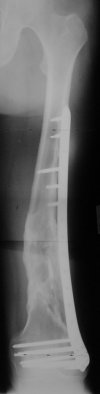

I presented a series of ~25 such cases at EuroTrauma'2004. Many cases were discussed here. I attach am example. Look also recent cases at http://www.hwbf.org/hwb/conf/alex58/scfx.htm,

THX, initial images are

1,

2.

At that moment we had in stock only the 10 mm solid nails so of course there was no idea about early weight bearing. But it was quite enough for early knee ROM excersises (see attached). Two locking screws through the distal block provided that.